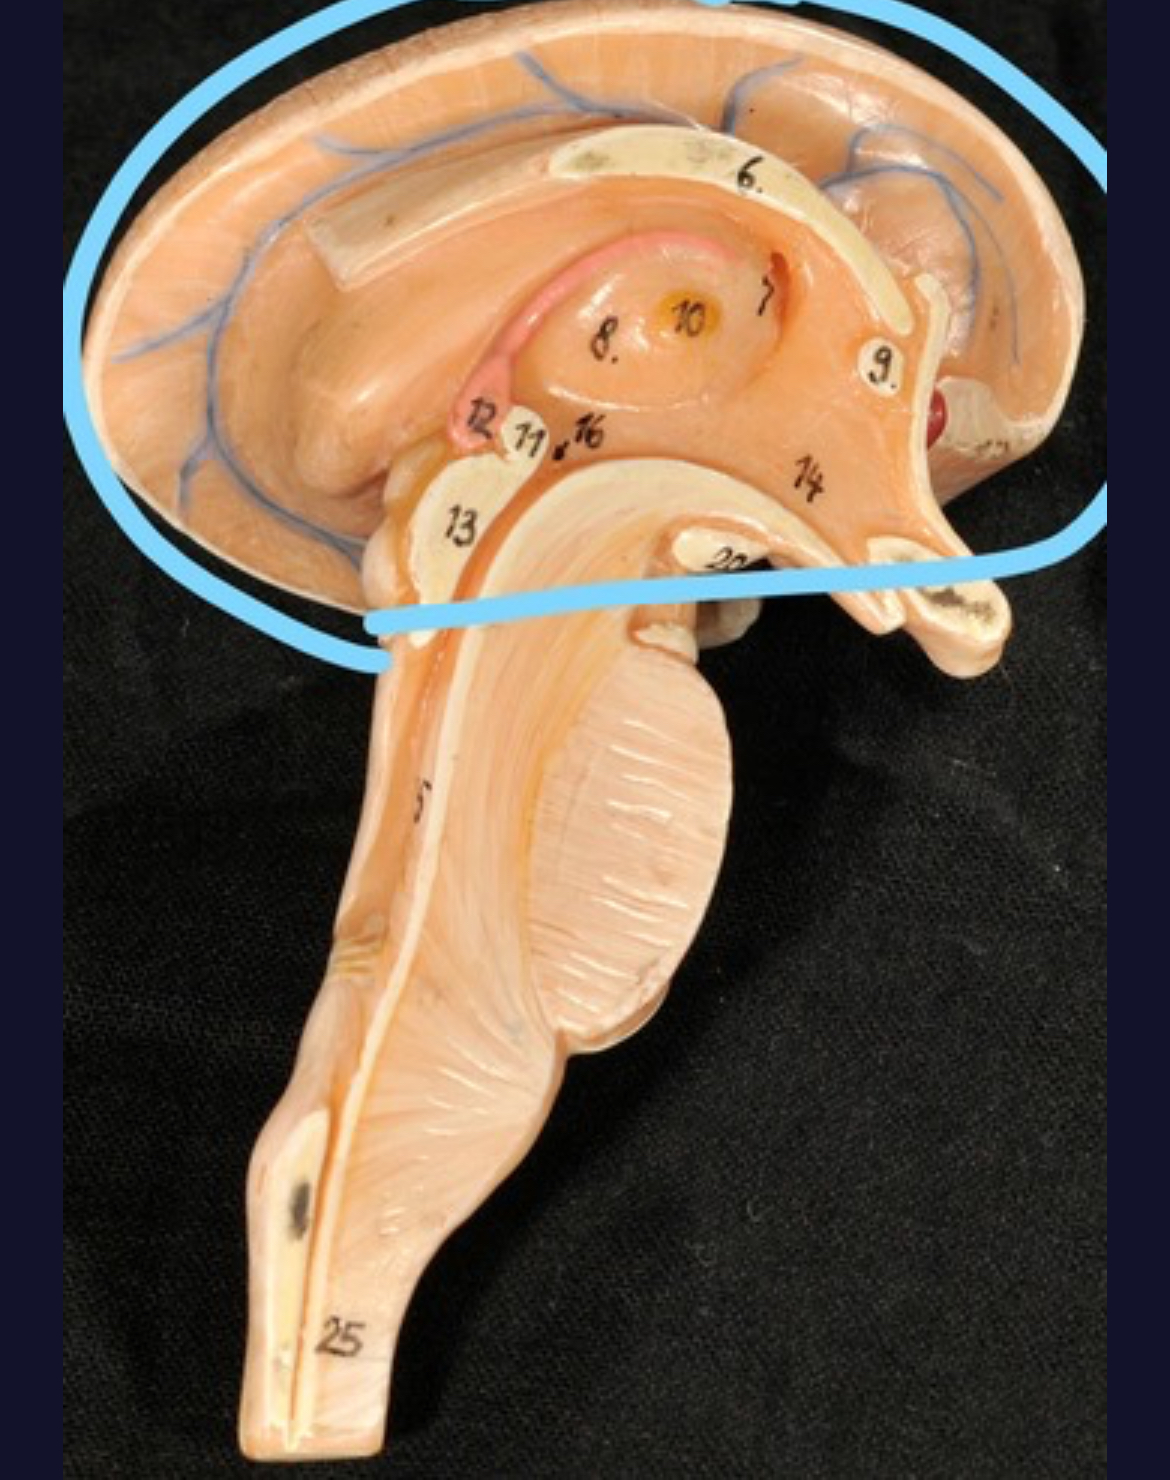

Corpus callosum

Diencephalon

Thalamus

3rd ventricle

Hypothalamus

Epithalamus (pink line)

Brain stem

Pons

Thalamus

Left lateral ventricle

Right lateral ventricle

Anterior horn of ventricle

Posterior horn of ventricle

Inferior horn of ventricle

Third ventricle

Cerebral aqueduct

Fourth ventricle of stick model

Dural sinuses

Spinal cord

Cauda equina